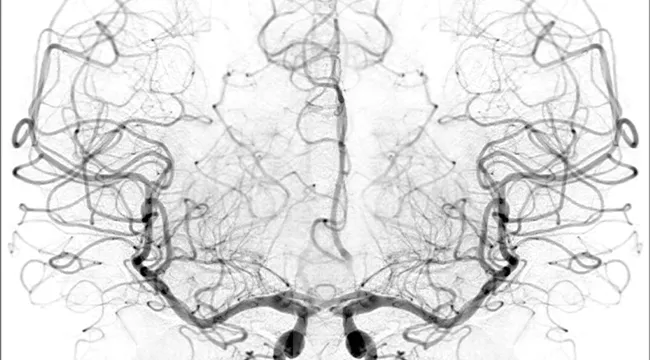

Genetic Engineering & Biotechnology News reports that researchers headed by teams at the University of Southern California Neurorestoration Center and at California Institute of Technology (Caltech) have built a simple, noninvasive tool for measuring blood flow in the brain—critical for understanding response to a range of neurological problems, including stroke, traumatic brain injury (TBI) and vascular dementia. The tool is based on a technique known as speckle contrast optical spectroscopy (SCOS), which is currently used in animal studies and has been adapted for potential clinical use in humans. Co-author Jonathan Russin, M.D., now professor and chief of neurosurgery at the University of Vermont, continues to collaborate with the USC Neurorestoration Center.